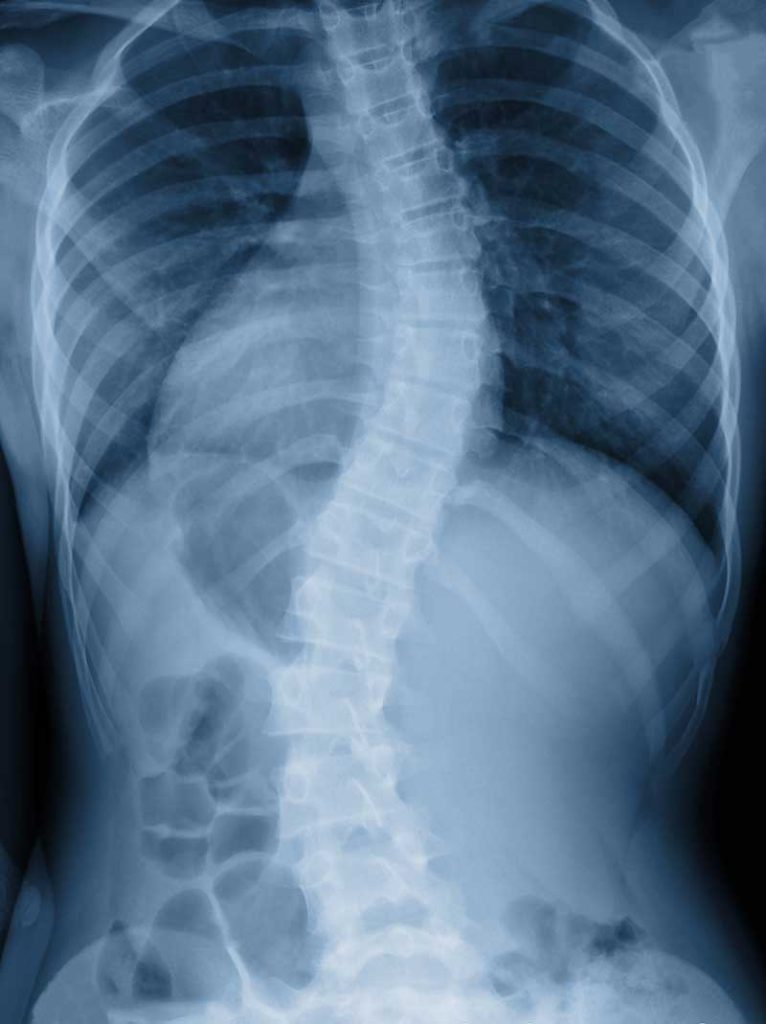

Scoliosis is a condition that is characterized by a curvature of the spine, often causing pain and discomfort. It typically occurs during early childhood, so checking for warning signs of scoliosis in young children is imperative. However, it is certainly possible that scoliosis can fly under the radar until adulthood. You may have scoliosis if you notice any of the following symptoms:

- The appearance of a twisted spine